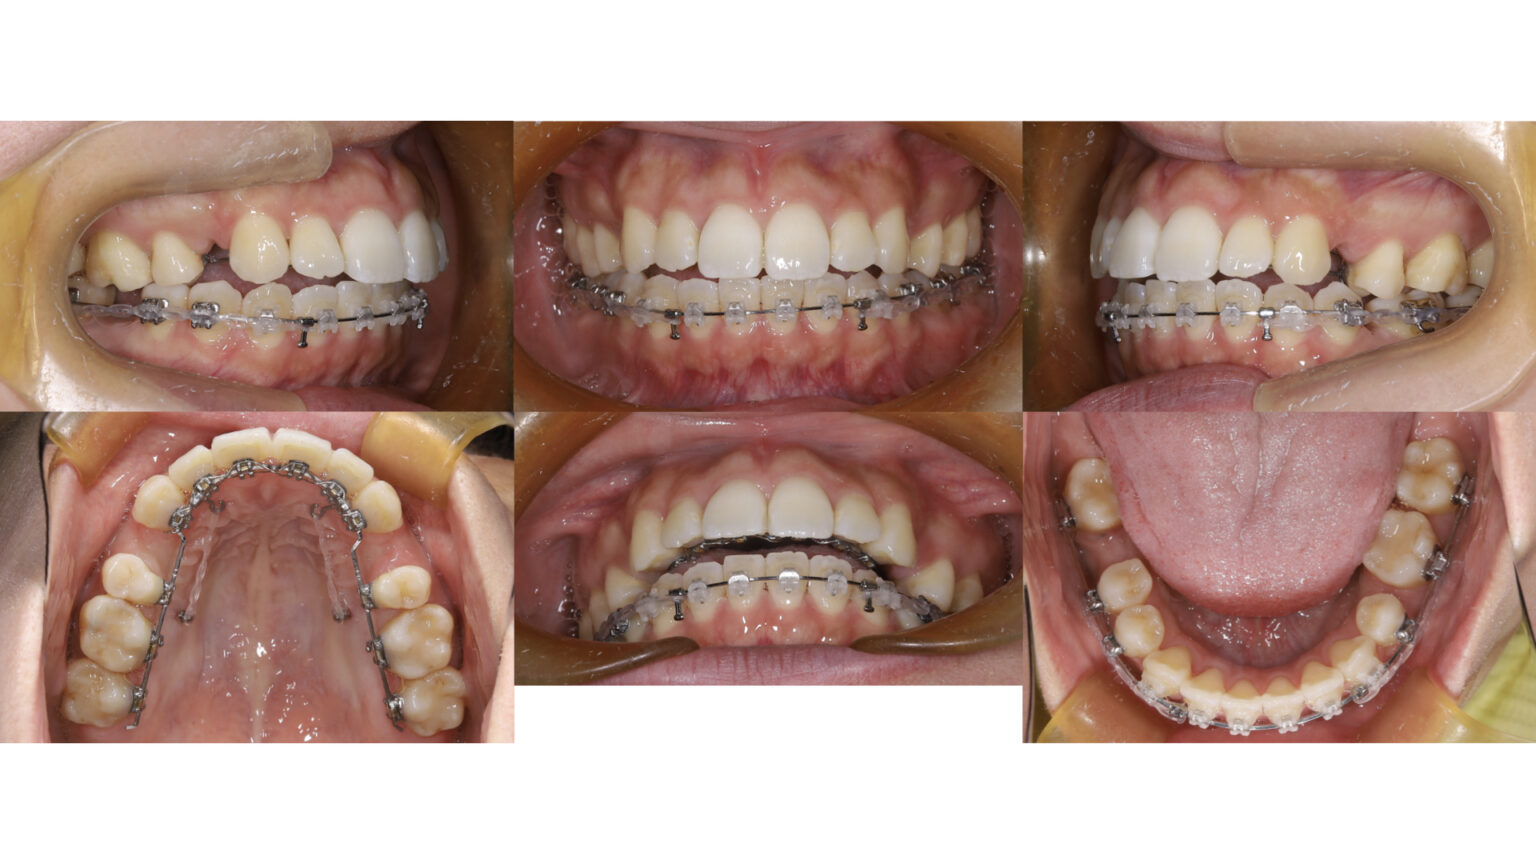

■ 治療経過

上顎にはリンガルブラケット、下顎にはラビアルブラケットを装着し、抜歯スペースの閉鎖を行いました。

また、上顎前歯の後方移動には矯正用アンカースクリューを併用し、確実な移動を図っています。

■ 治療結果

治療終了後の口腔内では、

・上下前歯の良好な咬合関係

・下顎右側第一大臼歯部のスペース閉鎖

・左右犬歯関係の改善

が得られました。

また顔貌においても、口元の突出感が改善し、調和の取れたプロファイルが獲得されています。